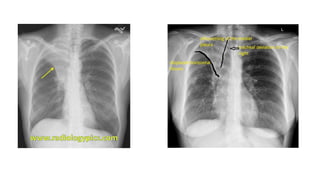

The document presents a chest X-ray examination summary by Ninian Peckitt, detailing various respiratory conditions including tracheal deviation, pleural effusions, and lung collapses. Findings suggest thoracic trauma and hyperinflation in the lungs. Additionally, it includes links to medical products and their pricing.